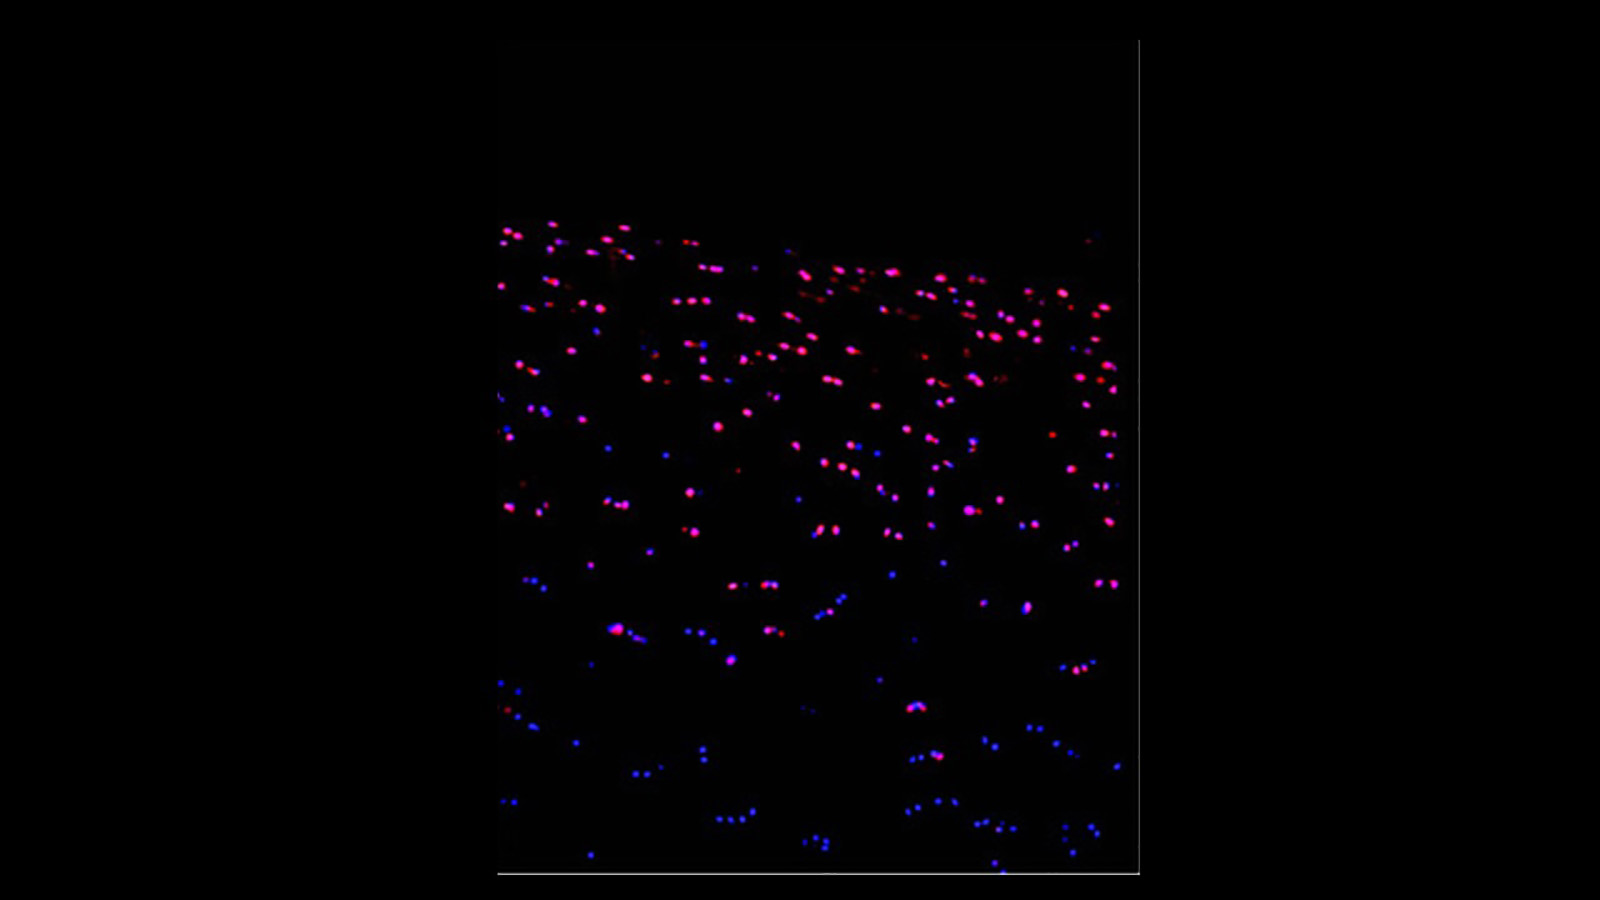

Imaging mass cytometry image of the placenta, courtesy of Santhosh Sivajothi of the Robson lab at JAX